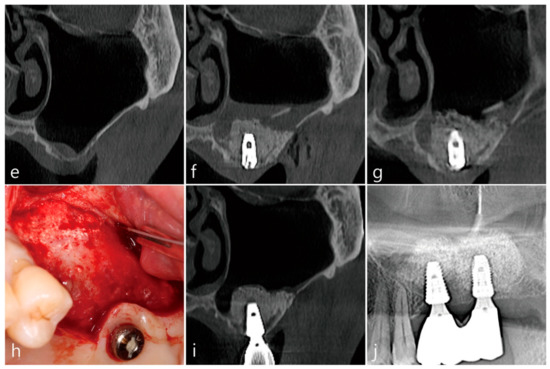

A 43-year-old male smoker visited the private clinic due to severe tooth mobility and chewing discomfort. On the pre-operative panoramic radiography, alveolar bone resorption was very severe due to advanced periodontitis and the height of residual bone was about 1–2 mm. Maxillary upper left, first molar tooth was missing (Figure 1a). A panoramic image of the preoperative CBCT showed no thickening of the left and right maxillary sinuses and severely pneumatized sinus (Figure 1b). During the lateral window approach for sinus floor elevation, the Schneiderian membrane was widely perforated during sinus floor elevation and the lateral bone lid was pushed up while attached to the sinus membrane. Implant site preparation was performed before filling the bone graft substitute. The osteotomy site was undersized drilled. Bone grafting using Osteon III (Genoss, Suwon, Korea) was performed on the sinus floor and the upper part of the lateral window was opened. Two 4.8 × 10 mm implants (Implantium, Dentium, Suwon, Korea) were installed (Figure 1c). On panoramic radiography taken immediately after surgery, bone graft substitute supporting the implants on the sinus floor was observed (Figure 1d). Patient reported minimal nasal bleeding and moderate facial swelling until 3 days after surgery. No other clinical events were reported during the healing process. Second stage surgery for uncovering of implants was performed 6 months after surgery. Implant placed at left upper second molar osseointegrated, but the implant at the left upper first molar was removed due to loss of osseointegration and immediately replaced with a wider 6.0 × 10 mm implant. On the coronal image of the left maxillary sinus CBCT before surgery at the first molar site, no sinus membrane thickening was noted, and the thickness of the buccal bone was thin (Figure 1e). Coronal image of CBCT immediately after MSA shows it in a state in which the Schneiderian membrane is irreparably perforated. A space between the elevated lateral bone lid and the sinus graft was observed, and displacement of the bone graft particles was not observed (Figure 1f). In the coronal image of CBCT 7 days after surgery, there was no leakage of bone graft substitute, and the sinus membrane thickening was insignificant (Figure 1g). The upper left maxillary first molar implant was uncovered after 4 months. At this time, the flap was reflected up to the opened lateral window site. The open lateral window site was closed with regenerated bone (Figure 1h). After 2 months of uncovering, the splinted prosthesis was delivered. In the CBCT taken immediately after the prosthesis delivery, the bone graft substitute was well consolidated without displacement and no volume change was observed (Figure 1i). In addition, the continuity of the buccal bone contour was well maintained at the lateral window site (Figure 1i). After 1 year follow-up, the patient’s chewing function was well maintained and no sinonasal complications were noted. No loss of marginal bone was observed on the panoramic radiograph (Figure 1j).

Figure 1.

Case 1. Preoperative and postoperative radiographic findings of case 1, and clinical pictures of the open lateral window technique. (a) On the preoperative panoramic radiograph, advanced periodontitis was accompanied by severe alveolar bone loss; (b) A panoramic image of the preoperative CBCT showed no thickening of the left and right maxillary sinuses; (c) The sinus membrane was widely perforated during sinus floor elevation. Bone grafting was performed on the sinus floor and the upper part of the lateral window was opened; (d) Panoramic radiograph after MSA and implant placement at the same time. (e) On the coronal image of the left maxillary sinus CBCT before surgery, there was no sinus membrane thickening and the thickness of the buccal bone was thin; (f) Coronal image of CBCT immediately after MSA in a state in which the maxillary sinus membrane is widely perforated. No leakage of bone graft substitute was found; (g) Coronal image of CBCT 7 days after surgery. There was no leakage of bone graft substitute, and the maxillary sinus membrane thickening was insignificant; (h) After 6 months of operation, uncovering was performed by tissue punching method, but explanation was performed due to osseointegration loss of implant #26, and re-implantation was performed immediately with a Ø 6.0 × 10 mm. At this time, the previous lateral window site was confirmed by reflecting a buccal mucoperiosteal flap. The exposed window site was completely covered with bone; (i) The prosthesis was delivered 4 months after the #26 implant re-implantation; (j) One year after the final prosthesis was installed, panoramic radiography showed that most of the bone graft substitute remained, and resorption of marginal bone around the implant was not observed.